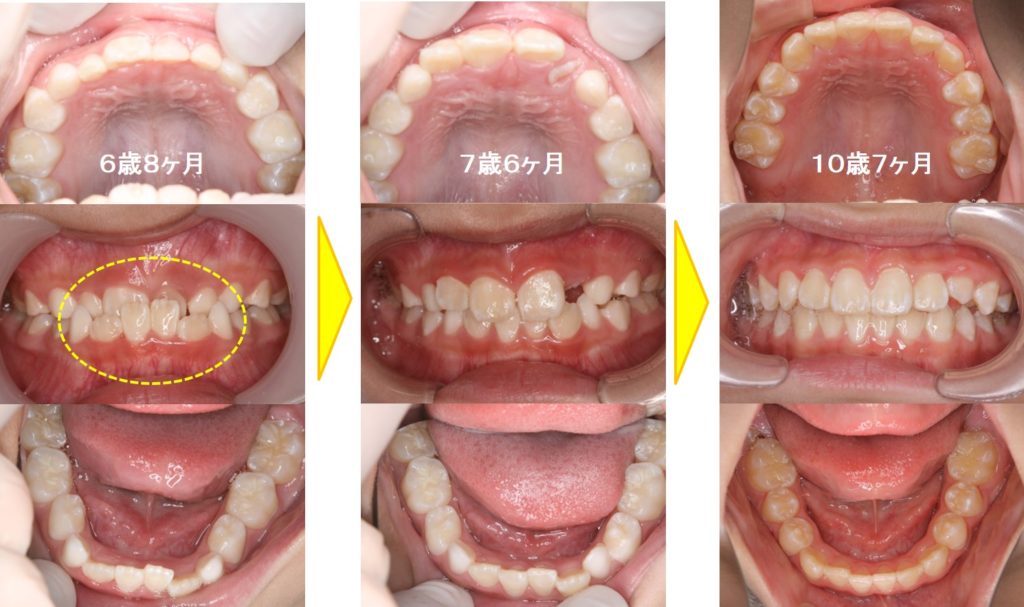

6歳8ヶ月の小学校2年生の男子の受け口症例です。母親が小学生のときに受け口の矯正治療をしていたそうです。前歯部分が完全に反対咬合(受け口)になっています。下あごの前歯はスペース不足でガタガタ(叢生)しています。床矯正装置を使用して約10か月で反対咬合は改善されました。その後もいくつかの装置を使い歯の生え変わりを利用しながら矯正治療を継続しました。乳歯が全て抜けてキレイな永久歯列になりました。

治療費:¥400,000 治療期間:3年11ヶ月

副作用・リスク:親知らずが生えるころに歯並びが乱れることがある